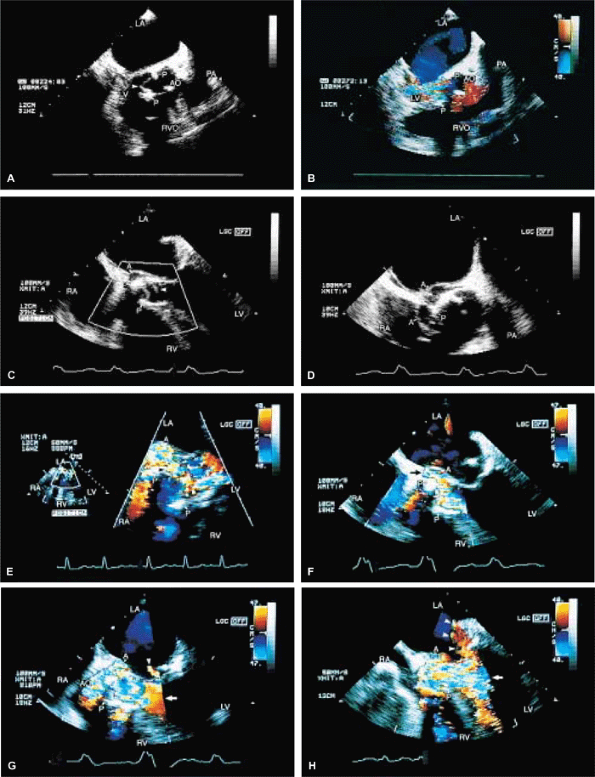

FIGURE 5.2. St. Jude mitral prosthesis: thrombus. A–F. Localized echo densities consistent with thrombus (T) are noted on the St. Jude prosthesis (P) in two different patients (A,B and C–F). In both patients, thrombus prevented the opening of one of the leaflets of the prosthesis. F. Continuous wave Doppler shows a flat velocity profile in early diastole (arrows) and a high peak velocity of 152 cm/sec consistent with obstruction. G and H (one patient) and I (another patient) show two other patients with thrombosed (TH, T) St. Jude mitral prostheses. The echo densities representing thrombus are seen on the atrial side of the prosthesis. Thrombi are less dense than the metallic components of the prosthesis and are different from prosthetic reverberations, which are anteriorly directed, more prominent, and have larger linear echoes. In addition, reverberations are not seen on the atrial aspect of the prosthesis. AO, aorta; LA, left atrium; LV, left ventricle; MP, mitral prosthesis; RA, right atrium; RV, right ventricle; RVO, right ventricular outflow tract. |

FIGURE 5.7. Bjork-Shiley mitral prosthesis: thrombus/pannus. A. A small echo density consistent with thrombus (T) is seen within the ring of the prosthesis (P). B. Its presence is confirmed by the flat diastolic velocity profile (arrows) and a high peak pressure gradient (16 mm Hg) across the prosthesis, consistent with obstruction. C–K. Another patient with a thrombosed Bjork-Shiley mitral prosthesis. Note the spontaneous contrast (SC) echoes in the left atrium (LA) in C, G, and J. I. A thrombus (TH) is well seen on the atrial aspect of the prosthesis (PMV) imaged with a probe in the esophagus, whereas the thrombus on the ventricular aspect is best visualized during transgastric examination (I).Another thrombus (TH) is present in the left atrial appendage (LAA) (G). Color Doppler–directed continuous wave Doppler reveals a very flat diastolic velocity profile with a very high peak velocity of 305 cm/sec, indicative of very severe flow obstruction. K. The arrowhead in J shows prominent flow acceleration on the atrial aspect of the prosthesis. R, prosthetic ring. L. Another patient with a Bjork-Shiley prosthesis. In this patient, the echo density on the ventricular aspect of the prosthesis (P) was found at surgery to be a pannus (PAN) rather than a thrombus. Spontaneous echo contrast (SEC) was present in LA. M. Gross specimen of a thrombosed mitral prosthetic valve. AO, aorta; LV, left ventricle; RV, right ventricle, spontaneous contrast. |